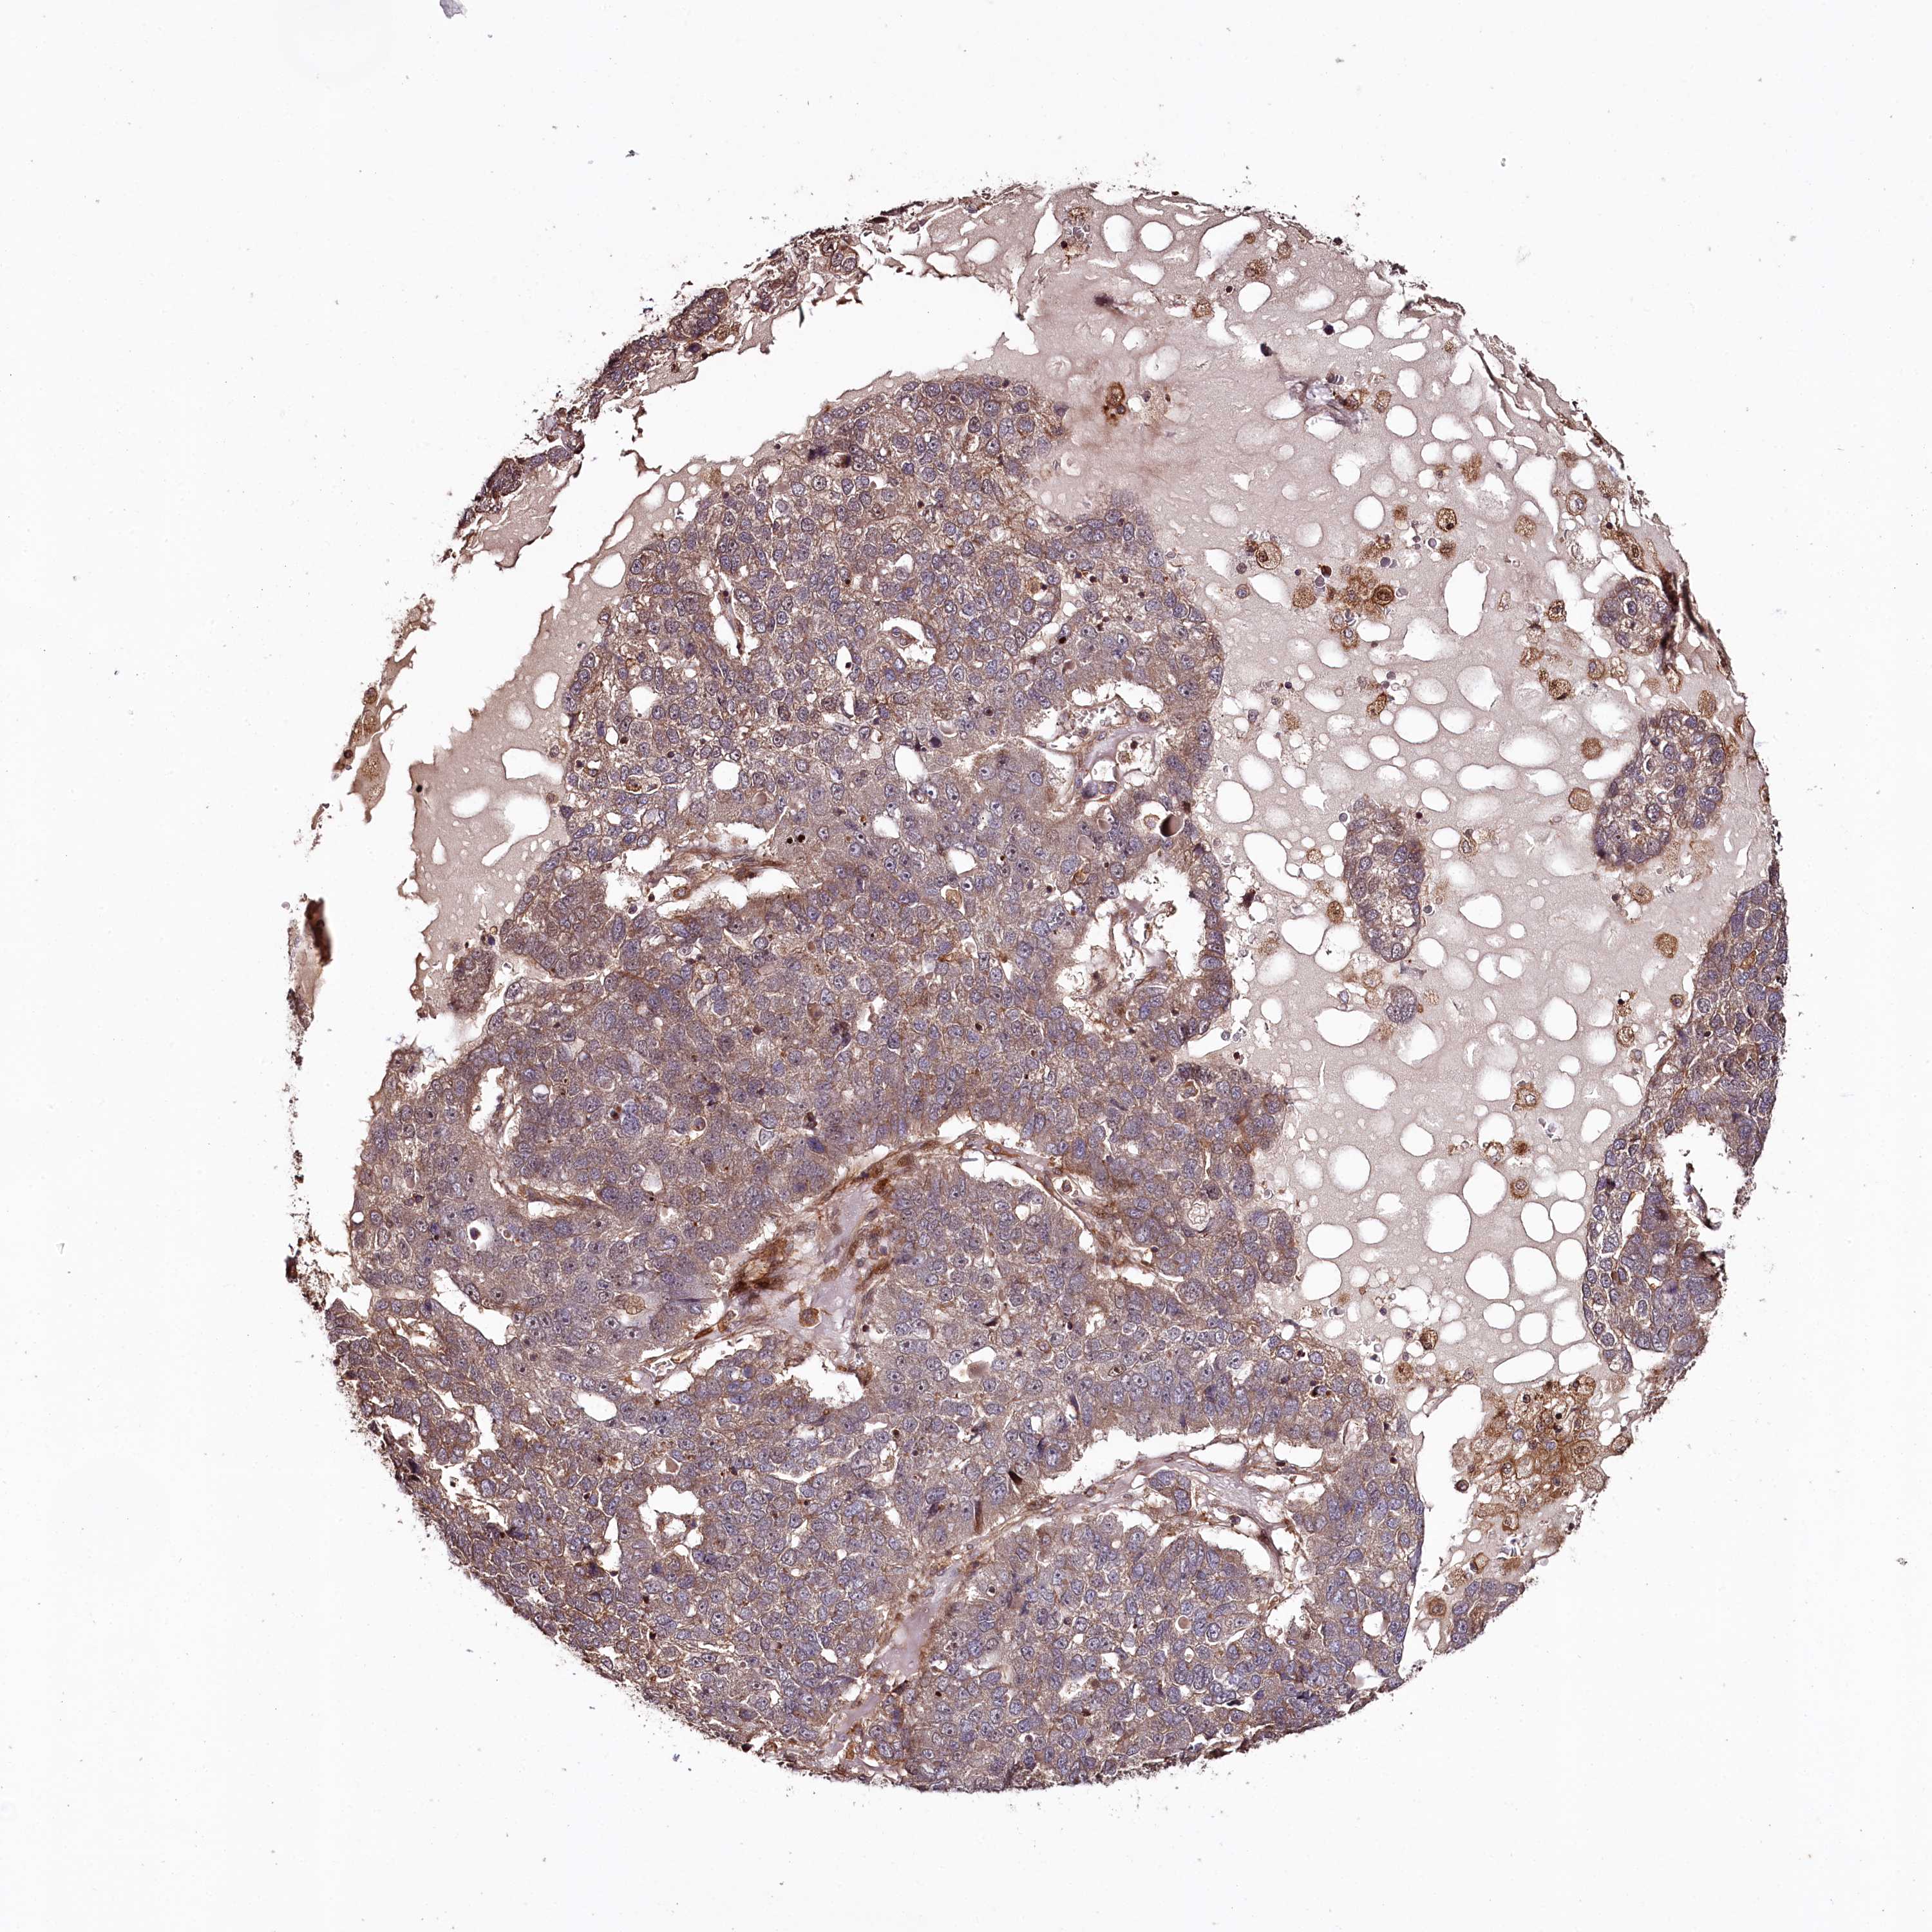

PANCREATIC CANCER - Protein expressioni

A mouse-over function shows sample information and annotation data. Click on an image to view it in a full screen mode. Samples can be filtered based on level of antibody staining by selecting one or several of the following categories: high, medium, low and not detected. The assay and annotation is described here.

Note that samples used for immunohistochemistry by the Human Protein Atlas do not correspond to samples in the TCGA dataset.

Antibody stainingi

Antibody staining in the annotated cell types in the current human tissue is reported as not detected, low, medium, or high, based on conventional immunohistochemistry profiling in selected tissues. This score is based on the combination of the staining intensity and fraction of stained cells.

Each image is clickable and will lead to virtual microscopy that enables deeper exploration of all samples and also displays staining intensity scores, fraction scores and subcellular localization as well as patient and tissue information for each sample.

Antibody HPA038061

Staining

High

Medium

Low

Not detected

Intensity

Strong

Moderate

Weak

Negative

Quantity

>75%

75%-25%

<25%

None

Location

Nuclear

Cytoplasmic/membranous

Cytoplasmic/membranous,nuclear

Adenocarcinoma, NOS